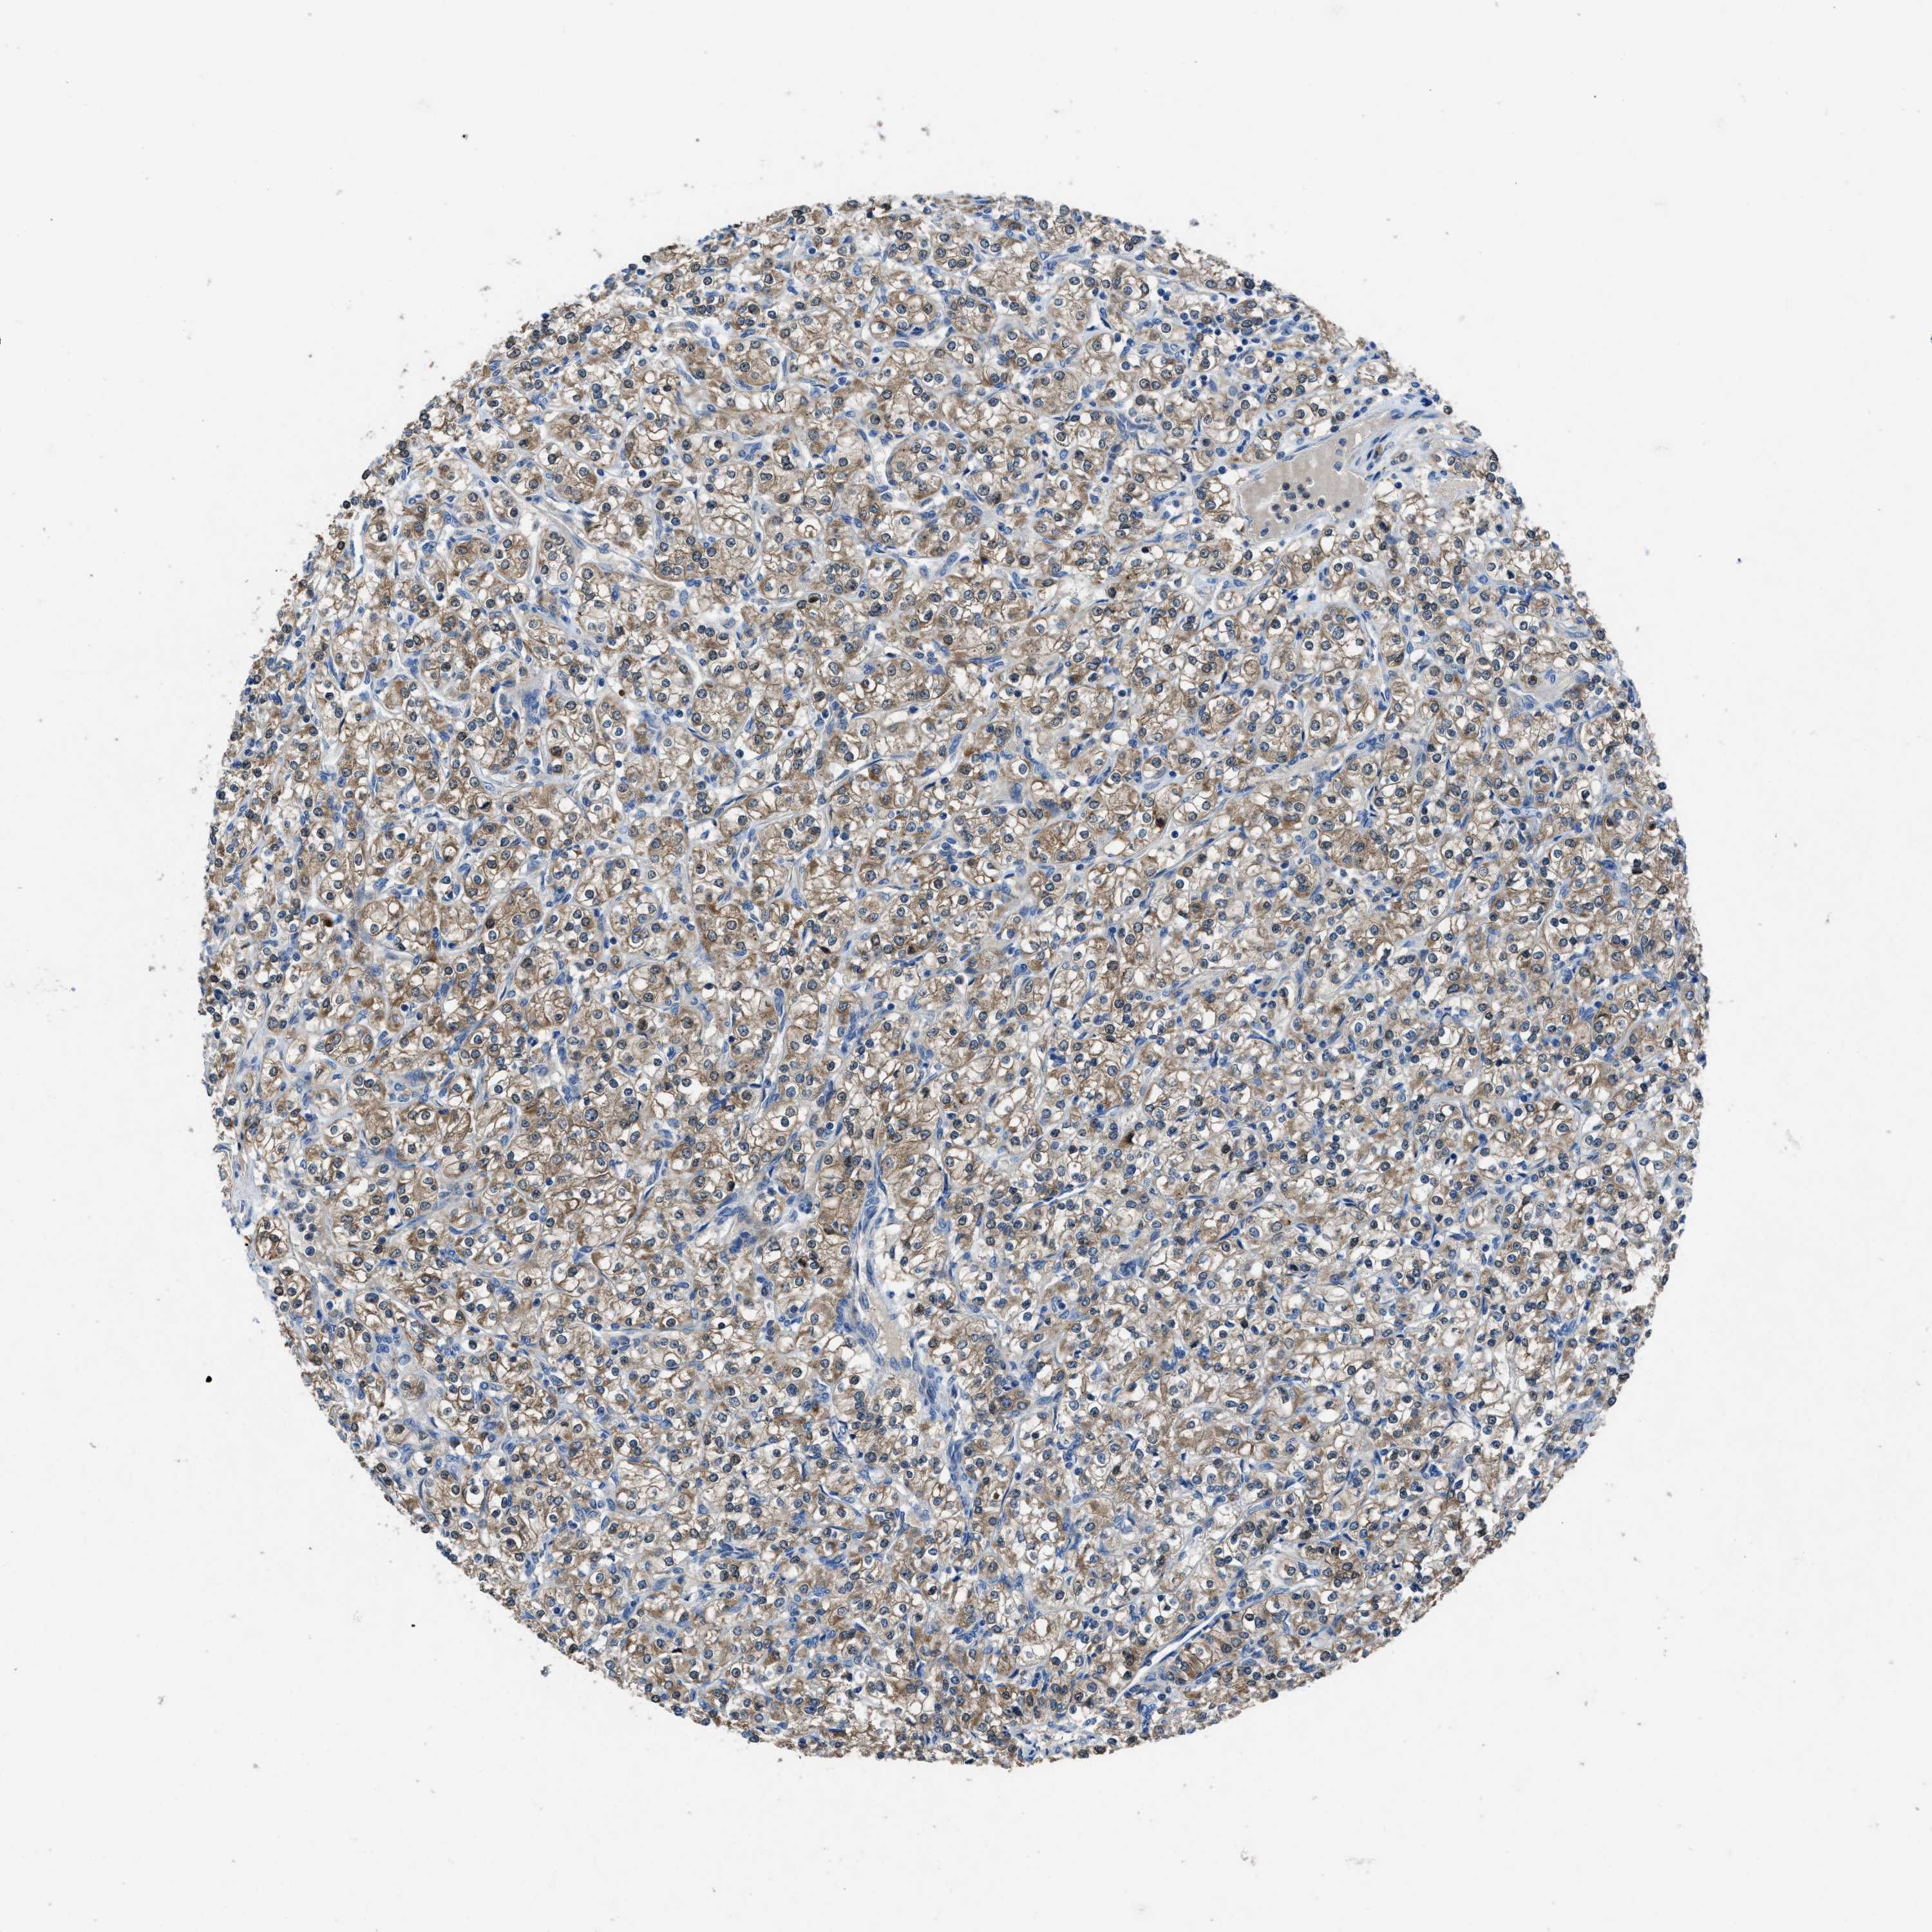

MAP3K20